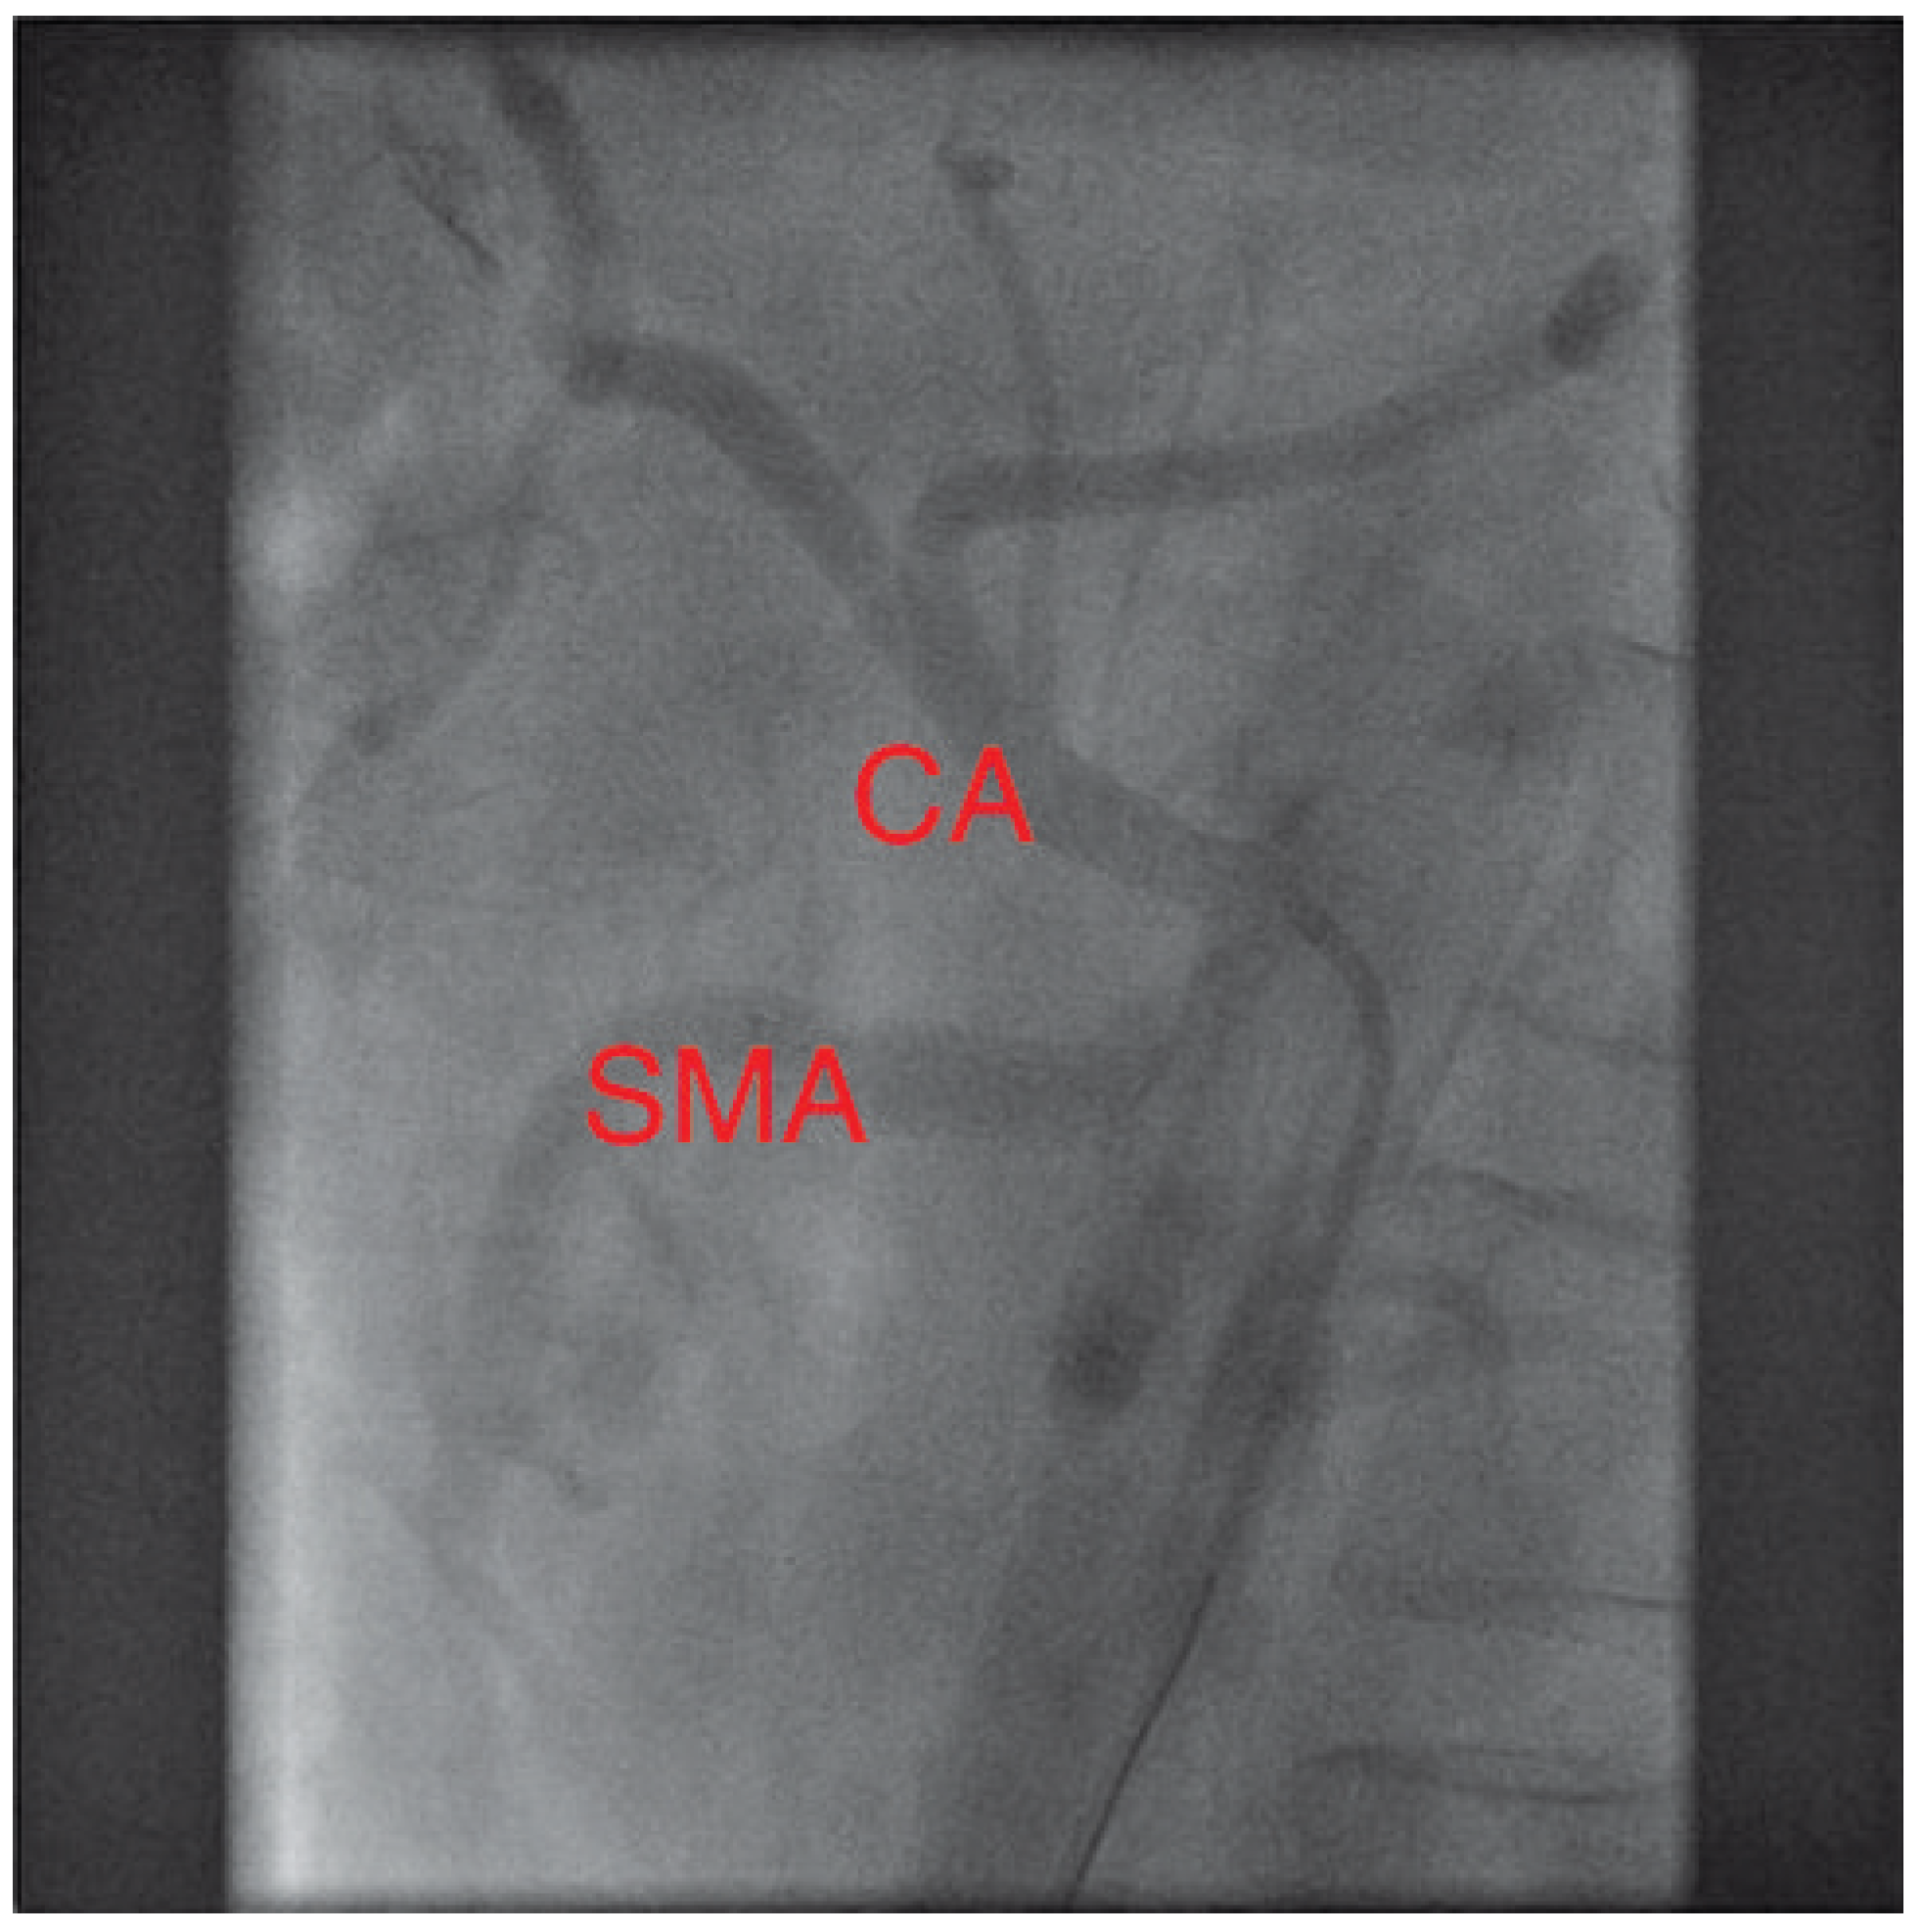

Figure 2. Same projection: again with a catheter (*) in place. After ballooning and stent implantation the stenosis is no longer visible.